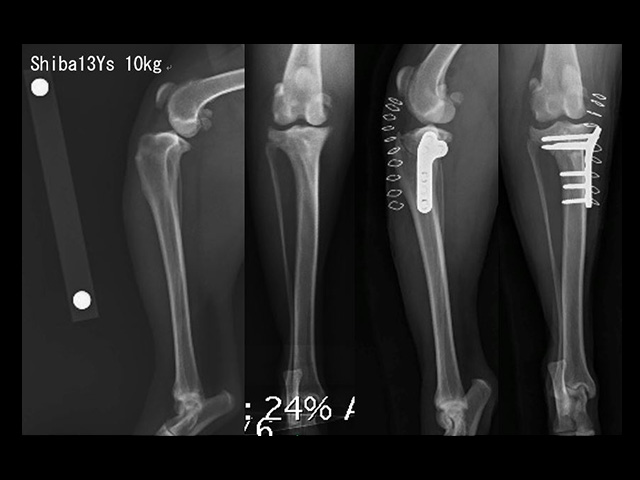

骨折Bone fracture

骨折症例の多くは、整復固定治療直後の運動機能回復と疼痛消失により、普段の活発さを取り戻します。従って、骨癒合までの間、活発さに耐えて初期固定を維持できる安定した固定法が求められます。